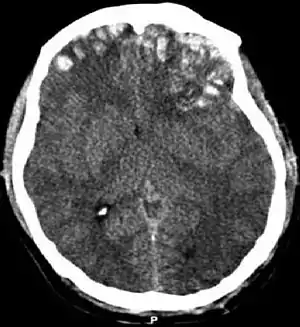

Contusão cerebral

A contusão cerebral, do latim contusio cerebri, é uma forma de lesão cerebral traumática.[1] A contusão ocorre em 20-30% dos ferimentos graves na cabeça. A lesão pode causar um declínio na função mental a longo prazo e, no cenário de emergência, pode resultar em hérnia cerebral, uma condição com risco de vida em que partes do cérebro são pressionadas para passar por partes do crânio.[2]